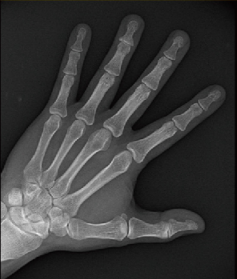

Hand X-Ray